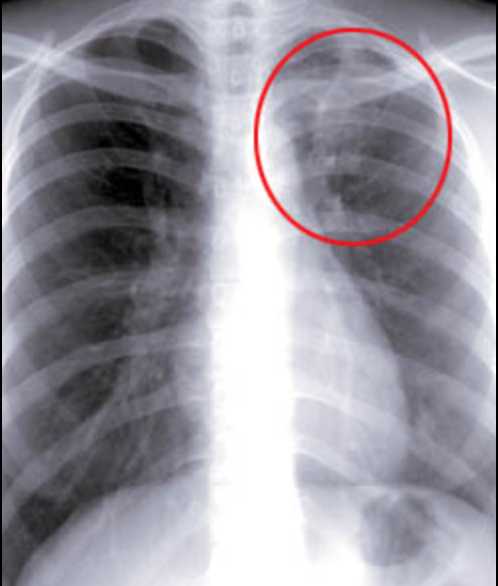

결핵이 의심된다면 흉부 엑스레이, 객담검사, 필요시 CT 검사까지 받을 수 있으며, 대부분 국가에서 검사비를 지원합니다.